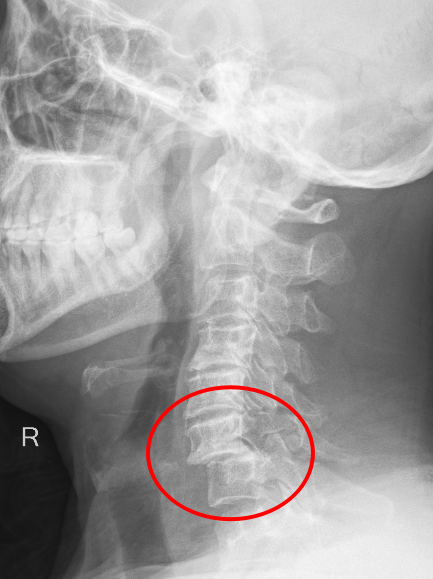

近日,重庆医科大学附属璧山医院(重庆市璧山区人民医院)骨科团队凭借精湛技术和默契协作,成功为一名高空坠落致颈椎重创的危重患者实施了高难度复位固定手术,术后患者恢复良好。